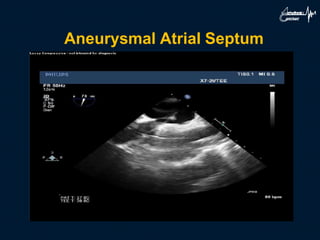

Aneurysmal Atrial Septum